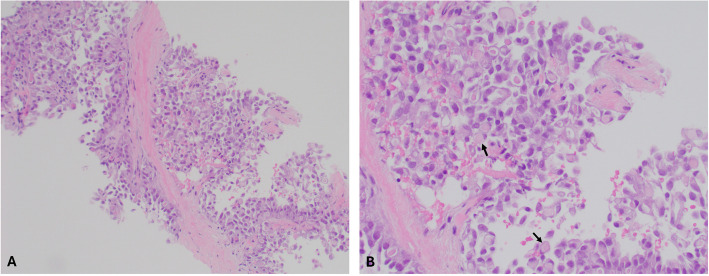

Results: A 63-year-old female presented with neck swelling and difficulty breathing. CT scan showed a large thyroid mass. Tracheal compression and deviation required stent placement and urgent radiation. Microscopic analysis showed neoplastic cells with frequent intracytoplasmic globules, including signet-ring cells. IHC stains were inconclusive to tumor type and metastasis from an occult primary was considered. However, PET-CT scan, mammography, and upper endoscopy were negative. Next-generation sequencing was performed revealing an ETV6-NTRK3 fusion favoring SC of the thyroid.